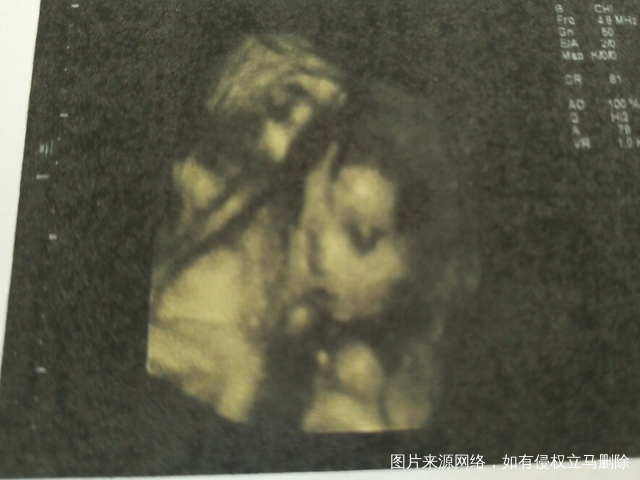

(● ●)最后我想说的“胎停”也许现在备孕

的麻麻们,也经历过,不要害怕,属于优胜劣

汰,调养好身体,继续备孕,祝帮里姐妹们每天开

心快乐心想事成(附我家宝宝第一张照片,男宝哦[调皮])